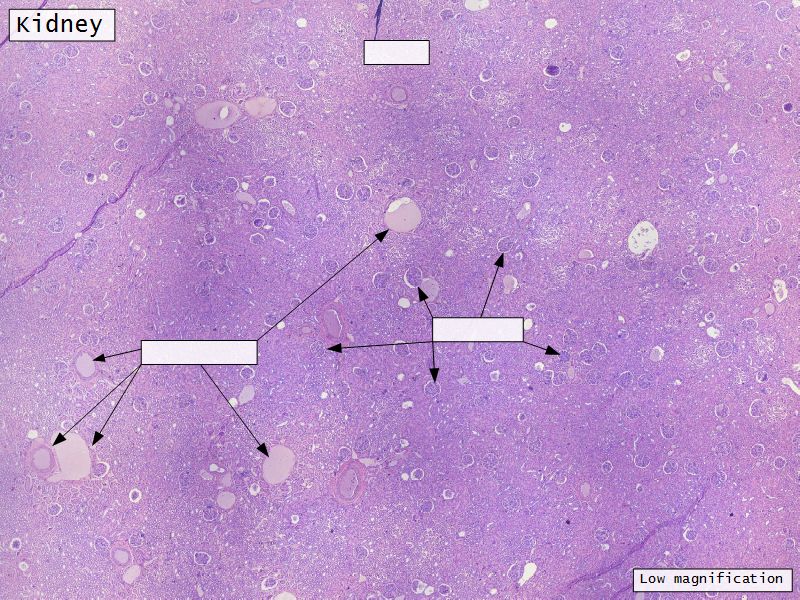

Appearance

- Cortex

- Renal corpuscles

- Convoluted tubules

- Medulla

- Loops of Henle

- Collecting tubules